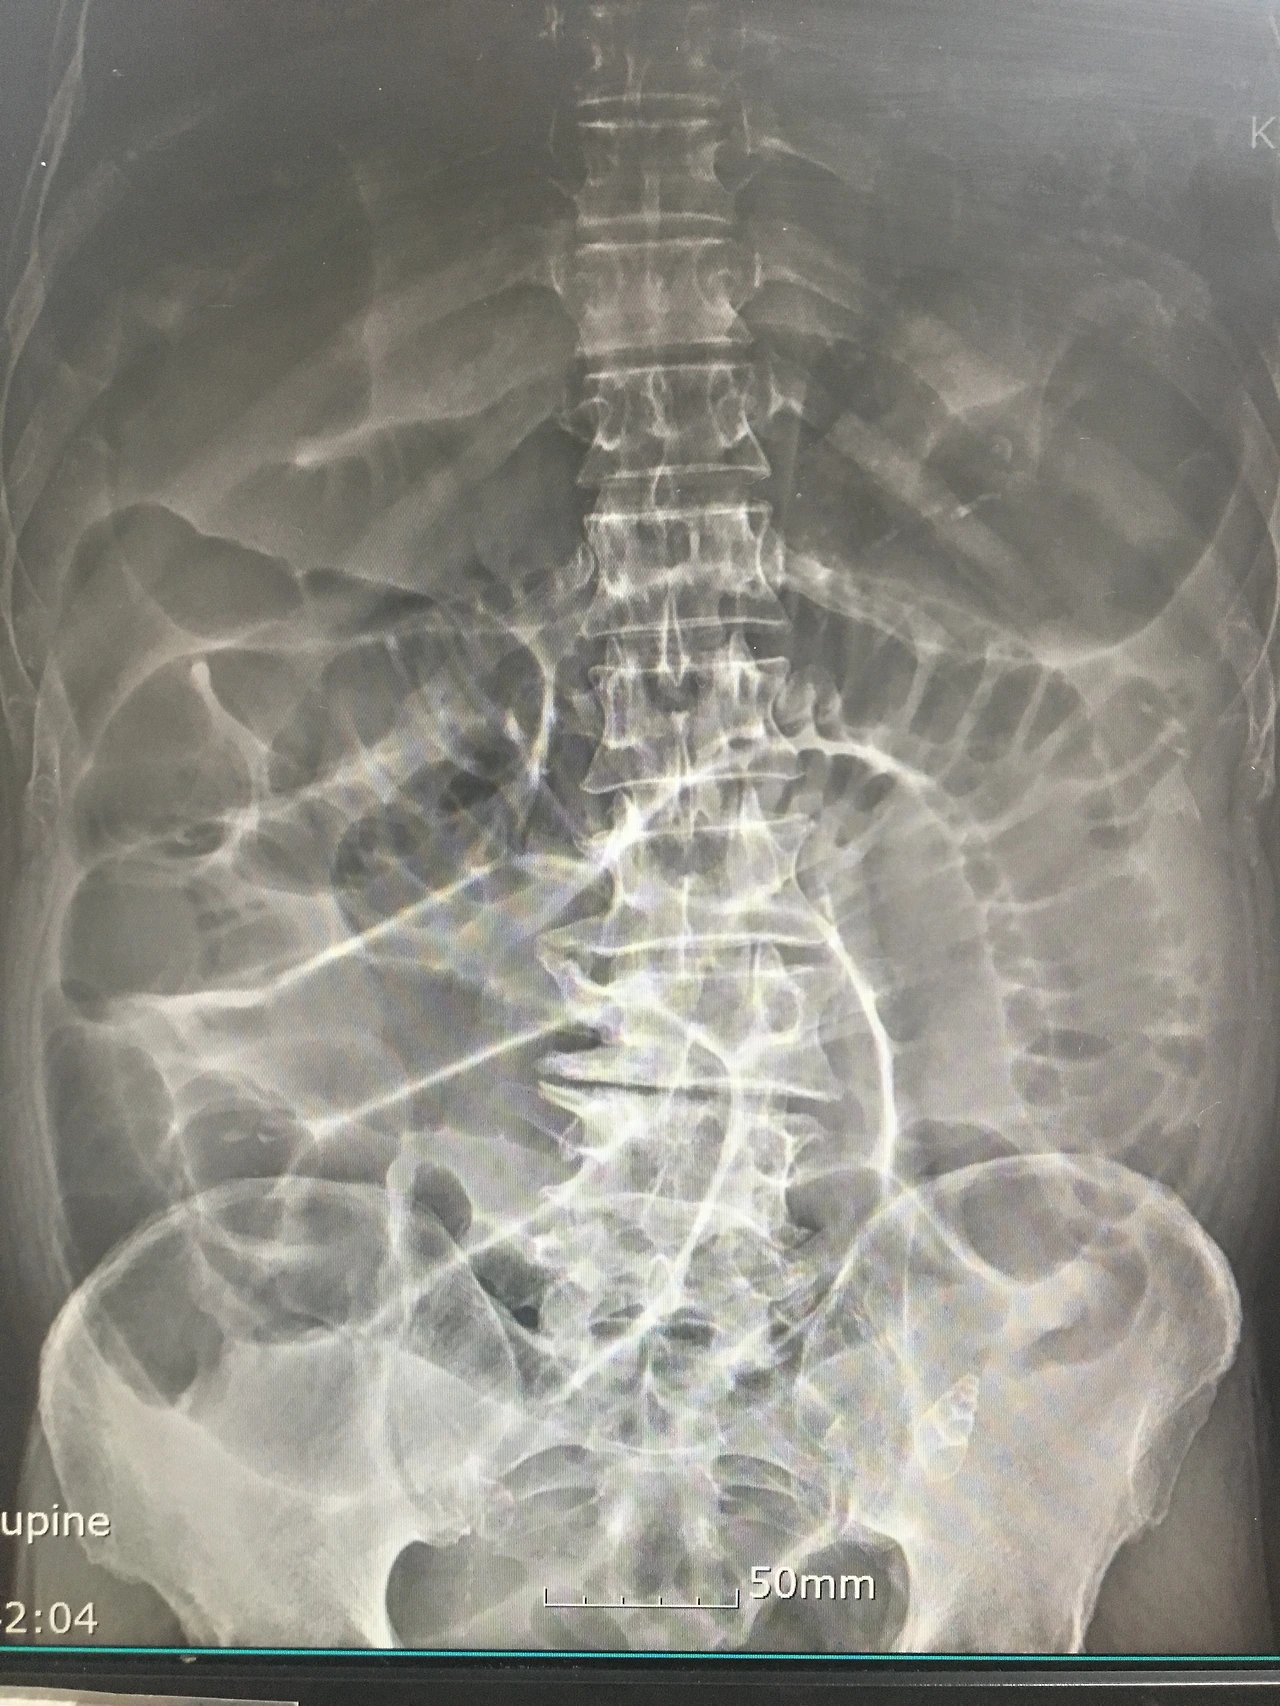

다슬기를 빨아먹다가 껍데기를 쏙 삼켰는데 그 뒤로 배가 아파 응급실로 왔다. x-ray 찍어보니 왼쪽 하복부에 다슬기 껍데기가 보이고 장폐색이 심해 보였다. 이어서 CT를 찍었는데 껍데기가 보인 부분에 대장암이 있었다. 대장암으로 좁아져 있던 곳을 껍데기가 꽉 막아서 생긴 장폐색이었던 것이다.